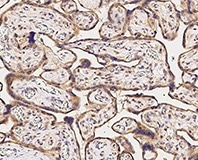

Anti-ACVR2B antibody, rabbit pAb

Applications

Cat#: 10229-T24

Immunochemical staining of human ACVR2B in human placenta. Image Credit: Sino Biological Inc.